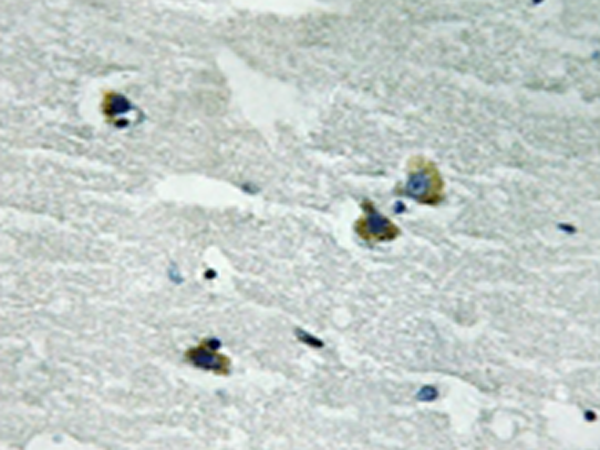

IHC positive control: |

Human brain tissue |

IHC Recommend dilution: |

50-100 |